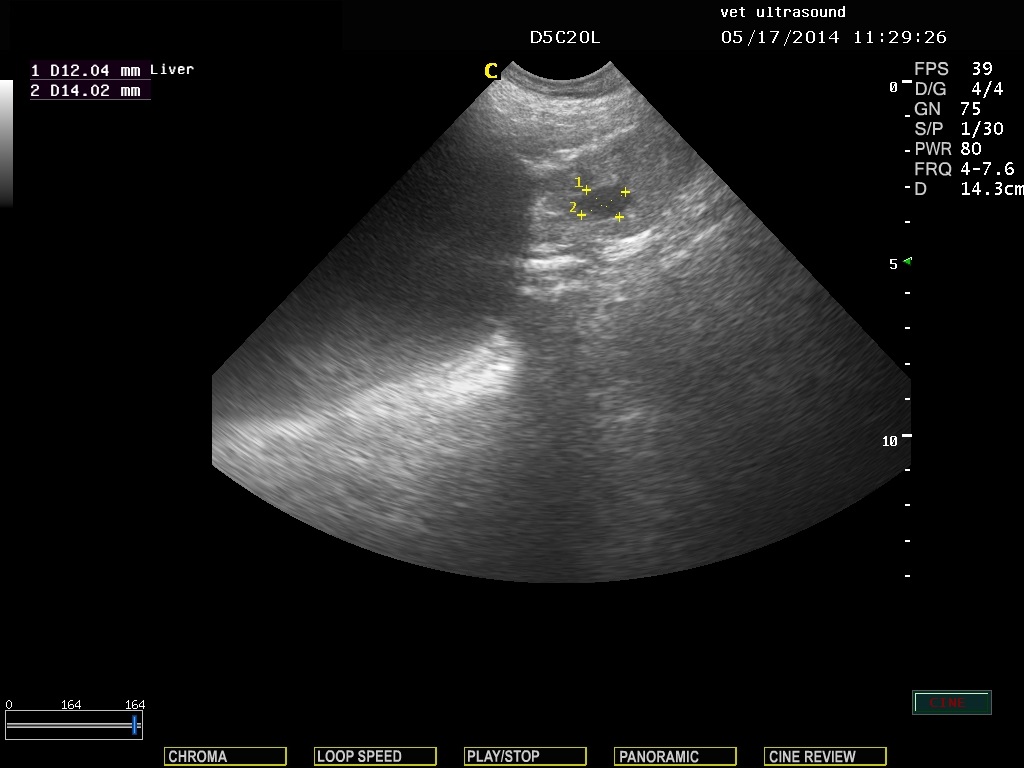

βλέπουμε την διατεταμένη ουροδόχο κύστη και τον προστάτη αδένα. Οι κέρσορες μετρούν το μέγεθος μίας κύστης στο παρέγχυμα του οργάνου.